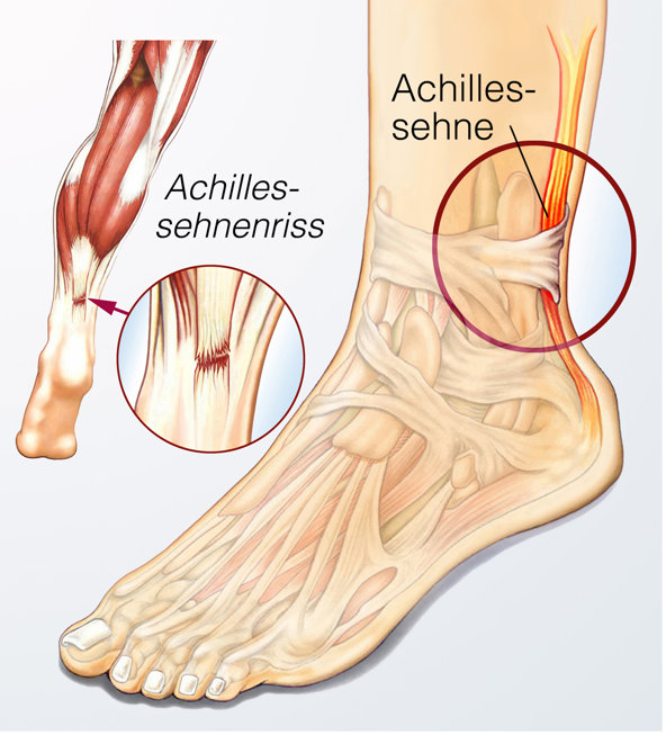

医学专家Brian Sutterer在个人的播客详细的分析了穆迪受伤的瞬间,他最终解析的结果是髌腱断裂而非向外侧移位的髌骨脱位,从机制上看当肌腱在被拉伸(离心)状态下,突然承受强烈收缩(向心),容易在极限负荷下发生断裂,这一点与跟腱断裂的受伤模式类似。

1.髌腱撕裂是指部分或小片肌腱纤维的完整性被破坏,而髌腱断裂则是指整个肌腱完全从骨附着点分离;

2.髌腱撕裂时,是相对轻微的组织损伤;而髌腱断裂通常伴有剧烈疼痛、肿胀和运动障碍;

3.髌腱撕裂后手术的难度不大,大概率是微创手术,而髌腱断裂的手术难度较大,如果微创手术无法修复需要进行开放性手术;

4.愈合的情况,髌腱撕裂经过适当的治疗与康复训练多数患者可以恢复正常的膝关节功能;而髌腱断裂可能会导致长期的运动功能障碍,甚至需要超长的康复过程。